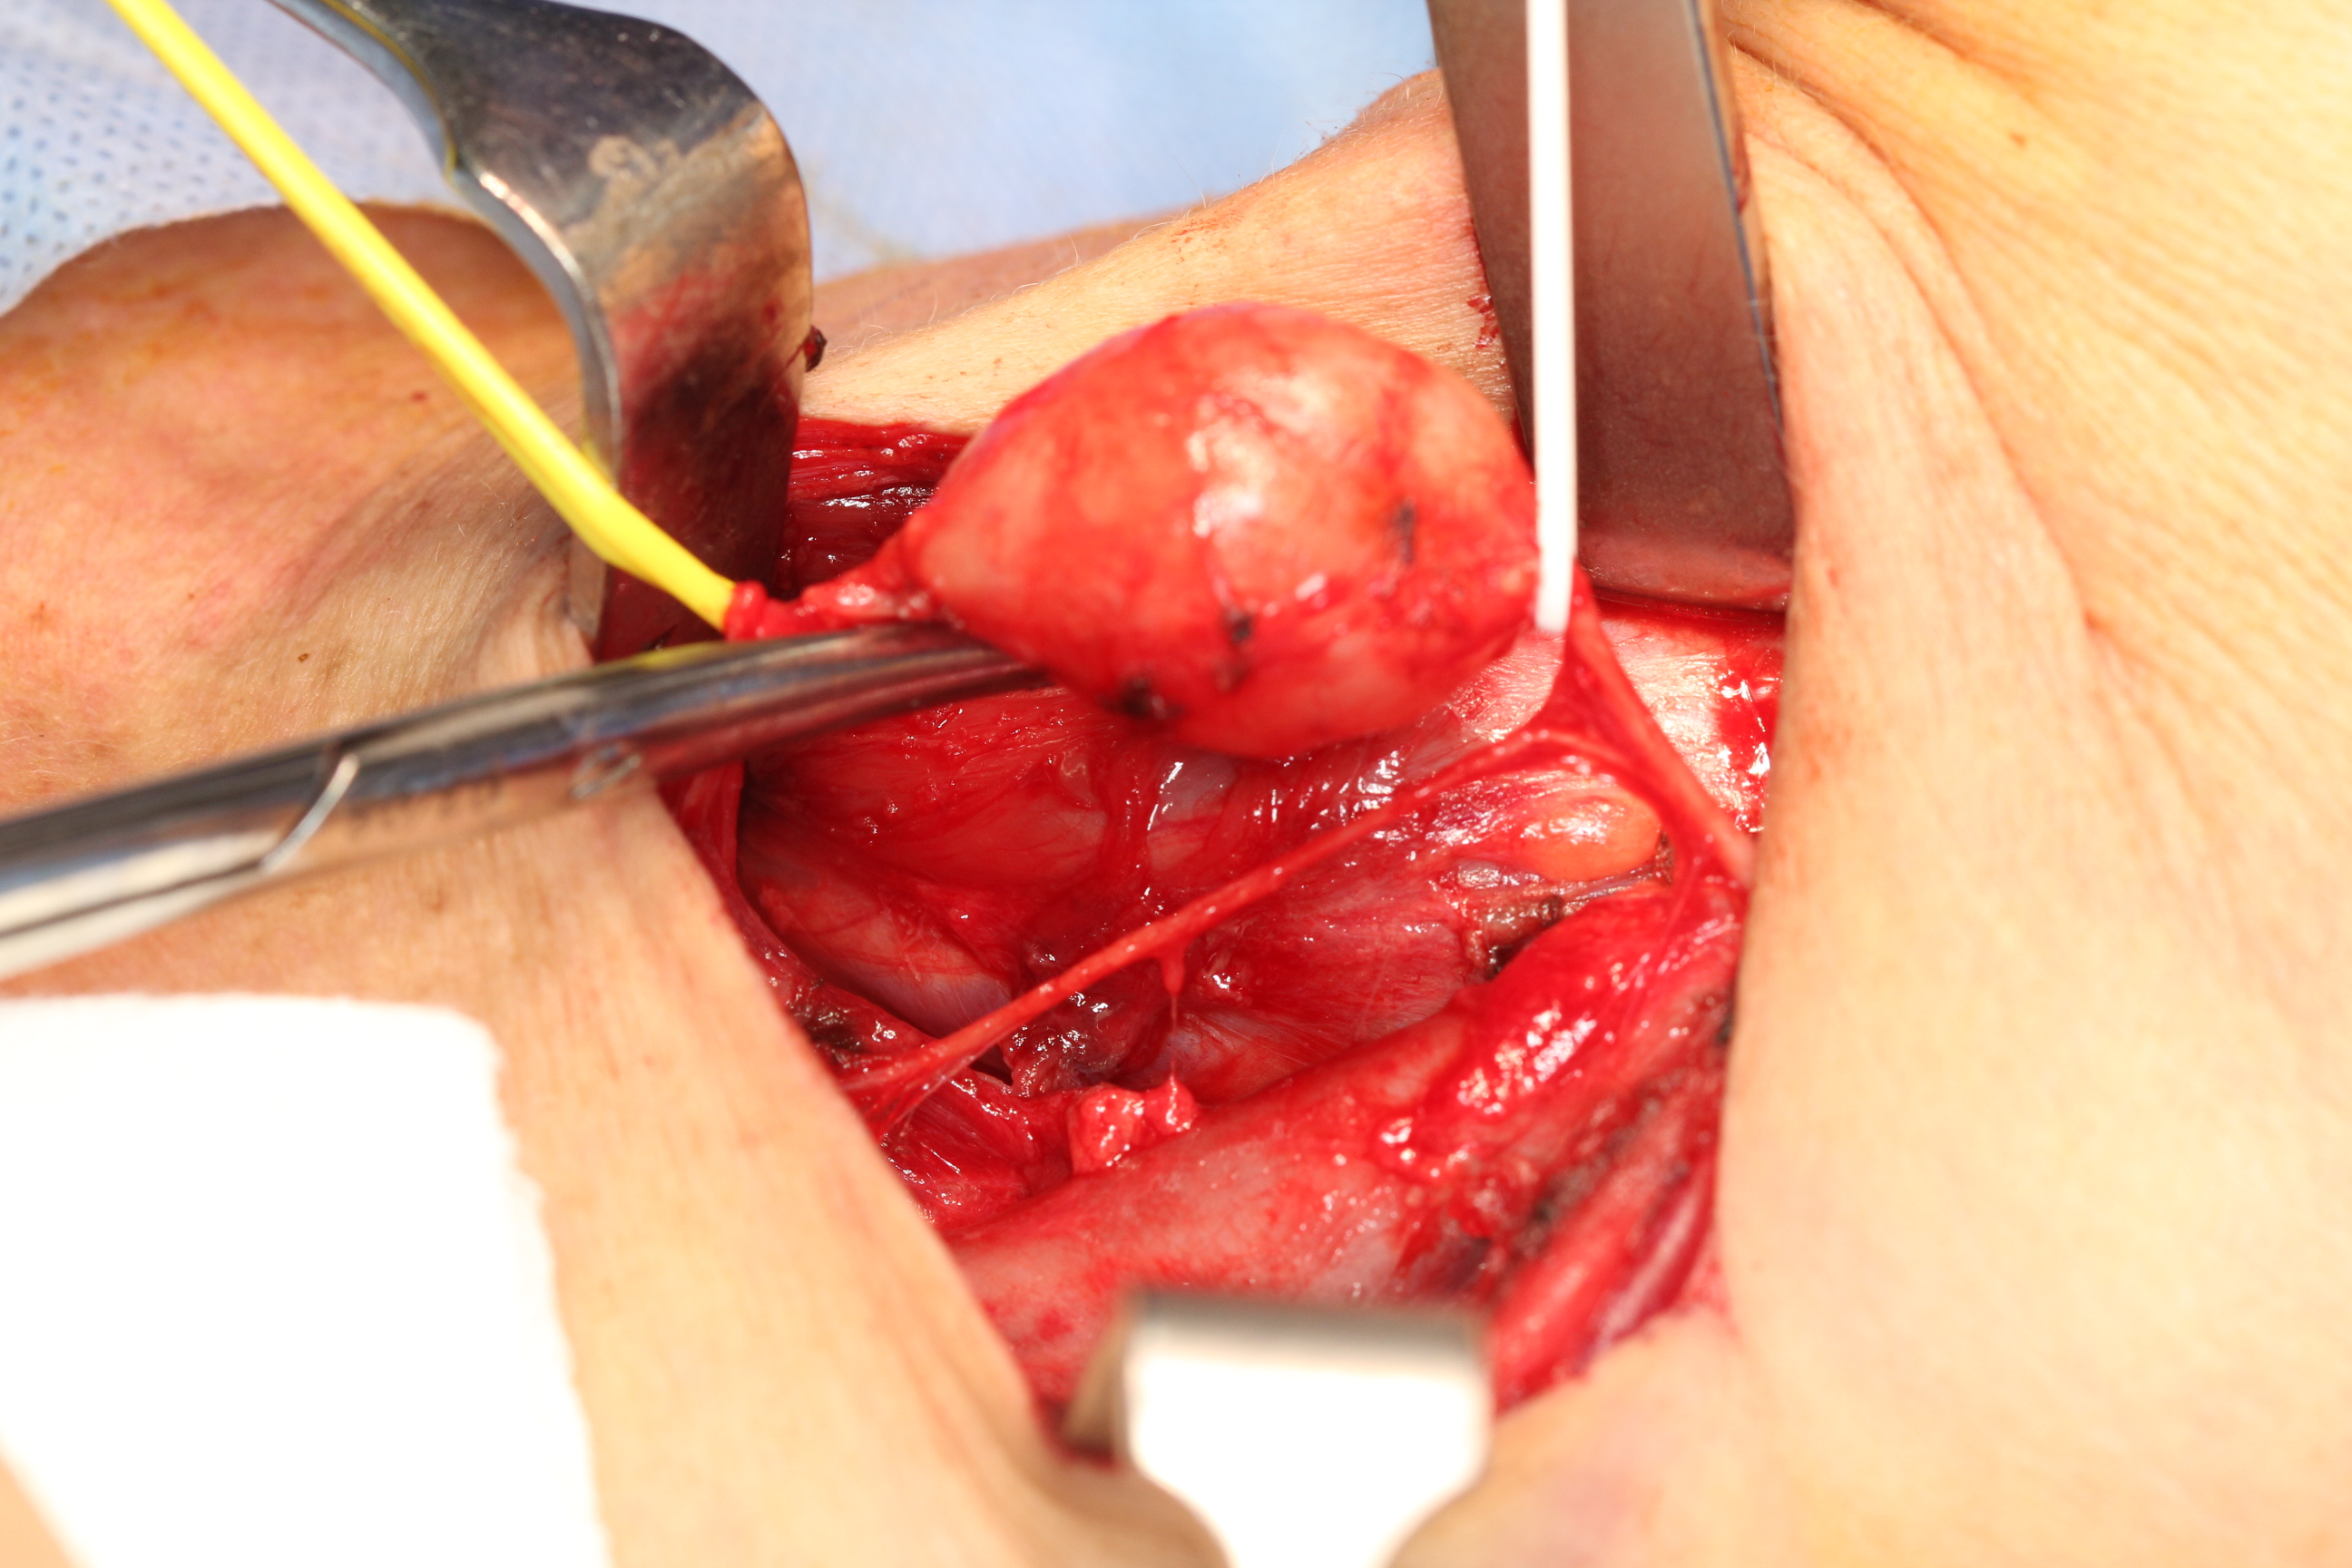

There are two main types of rhabdomyosarcoma, plus some rare variants. Embryonal rhabdomyosarcoma mainly affects young children but is the most common type at all ages. This variant is called ‘embryonal’ because of the characteristic appearance of the malignant cells, which resemble the developing muscle cells of a 6 to 8 week old embryo. The second main type, alveolar rhabdomyosarcoma occurs at all ages equally and accounts for approximately 20 to 30 % of rhabdomyosarcoma cases. It affects most commonly the head and neck region but also the extremities (see Figure 2). There does not seem to be a genetic predisposition for alveolar rhabdomyosarcoma.

Figure 2: MRI of alveolar rhabdomyosarcoma in a 4 year old child.